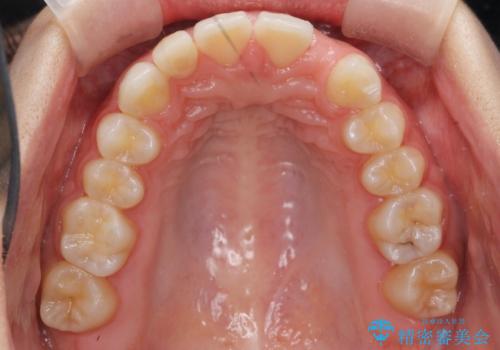

- 前歯の並びを主訴に来院。

前歯が出ており、また、左上の側切歯が1本生まれつき少ない状態でした。

また、右の奥歯の関係も上が前にある状態で大きくずれていました。

今回は左右とも1歯対2歯の関係であるため、それは変えずに前歯を可及的にひっこめて足りない部分をブリッジで補う治療としました。

奥歯の関係を完全に1級にするには右上の小臼歯の抜歯が必要でしたが、もともと左上の前歯が生まれつき少ないため今回は歯を抜かずに治療しています。